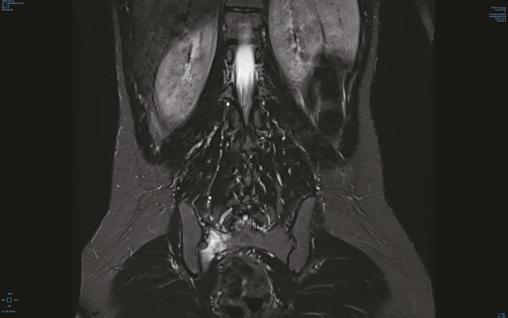

Engagée depuis 2 mois, cette jeune militaire consultait pour des paresthésies des orteils, sans notion de traumatisme aigu. Sédentaire auparavant, elle n’avait aucun antécédent particulier. Son indice de masse corporelle était de 20 kg/m2. L’examen notait une douleur neurogène avec trouble des sensibilités prédominant à l’extrémité du pied droit, sans syndrome radiculaire ni rachidien, d’horaire non mécanique. Le test de Faber était positif. Réalisée en seconde intention, l’IRM du bassin (v. figures) montrait une fracture de contrainte de l’aileron sacré droit. Le bilan biologique était sans particularité. Une cure courte d’anti-inflammatoires non stéroïdiens et la limitation au minimum des activités physiques entraînaient la guérison en 8 semaines.

La fracture de fatigue du pelvis est liée à un déséquilibre de l’homéostasie osseuse dans un contexte d’hypersollicitation. Elle est connue et sous-diagnostiquée chez les coureurs de fond (1 à 7 % de ces lésions), et les « nouveaux » sportifs notamment les jeunes recrues militaires.1 Le tableau clinique est non caractéristique et non spécifique. La radiographie standard ne permet pas de poser le diagnostic. L’anamnèse (changement, rythme, sport), le terrain et les signes négatifs orientent pour infirmer les diagnostics différentiels (discopathie, canal lombaire étroit, lésion cancéreuse).2 Six semaines de repos suffisent, en règle générale, pour guérir et reprendre progressivement le sport en charge. Toute femme ayant eu une fracture de stress doit bénéficier d’une exploration à la recherche du syndrome « triade de l’athlète féminine »(aménorrhée, trouble alimentaire et ostéoporose).